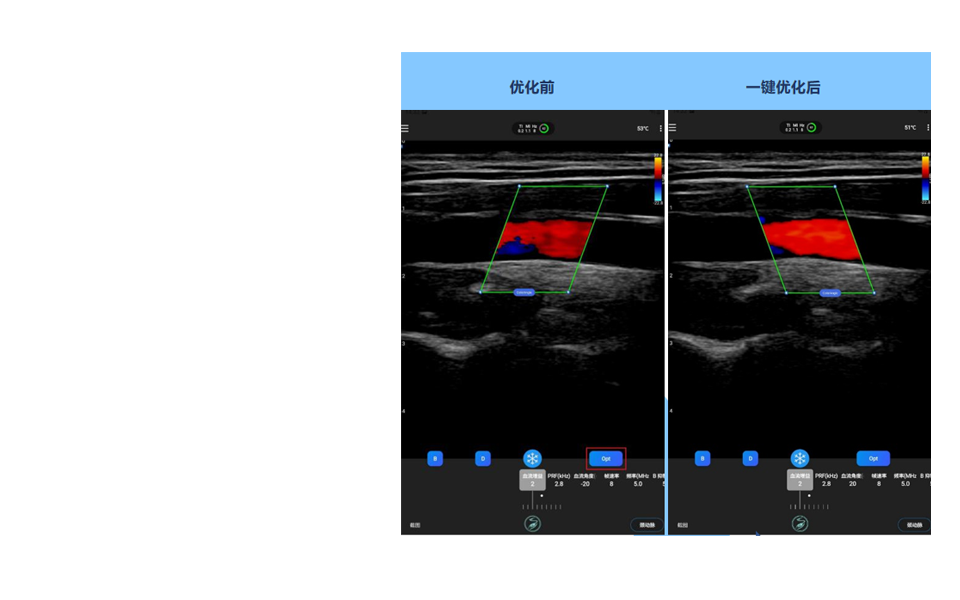

C模式的血流自动角度与位置识别AI一键优化功能

技术特点

方便C模式参数调节,减少用户调节角度与位置的复杂操作,AI会自动找到血管,进行角度与位置的调节。当进入C模式时,AI会自动调整C模式ROI到最佳位置,换言之,只要B模式打好血管,C 模式基本无需再调整角度与位置, AI会自动给出最佳选择。

当血管切面发生变化,点击Opt(Optimal)AI一键优化按键,AI会自动找到当前切面下,最佳的血流角度与位置,帮助用户免去繁复操作,获得最佳血流状态。